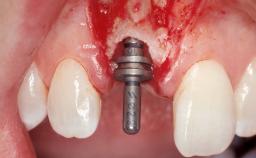

Late Flapless Placement of an Implant in a Maxillary Left Central Incisor Site

A 39-year-old male patient presented with a chief complaint of discomfort and gingival discoloration around his maxillary left central incisor. He was in good general health and was a non-smoker. His past dental history was significant because of the traumatic fracture of tooth 21 in a sporting accident at age 13. Initial dental treatment included endodontic therapy and a full-coverage restoration. The patient became symptomatic 5 years later, when structural failure of the tooth resulted in the dislodgment of the crown. Endodontic retreatment, apical surgery, and post-and-core restoration were performed.

Type of Implants One-Piece

Attachment One-Piece

Placement Protocol Early or late implant placement